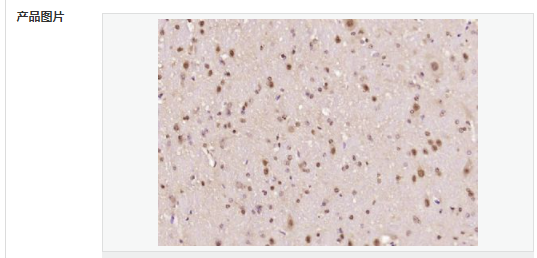

| 產品應用 | ELISA=1:5000-10000 IHC-P=1:100-500 IHC-F=1:100-500 ICC=1:100-500 IF=1:100-500 (石蠟切片需做抗原修復) not yet tested in other applications. optimal dilutions/concentrations should be determined by the end user. |

| 細胞定位 | 細胞核 細胞漿 |

| 產品介紹 | The human ataxin-7 gene, also known as spinocerebellar ataxia 7 or SCA7, maps to chromosome 3p13-p12, has a 2,727-bp open reading frame, and encodes a 892 amino acid protein containing a nuclear localization signal and a polyglutamine tract (1,2). SCA7 is an autosomal dominant neurodegenerative disorder characterized by ataxia and selective neuronal cell loss caused by the expansion of a translated CAG repeat encoding a polyglutamine tract in ataxin-7, which is the SCA7 gene product (3,4). Ataxin-7 is expressed within neurons both affected and unaffected in SCA7 pathology with subcellular localization being variable depending upon the neuronal subtype (5). Polyglutamine expanded in ataxin-7 may carry out its pathogenic effects in the nucleus by altering the matrix-associated nuclear structure and/or by disrupting nucleolar function (6). Function: Ataxin 7 is a protein of unknown function. It may be the human orthologue of the yeast SAGA SGF73 subunit and a subunit of the human TFTC-like transcriptional complexes. Spinocerebellar ataxia 7 (one of a group of hereditary neurodegenrative diseases) is caused by an expanded trinucleotide repeat in the gene encoding ataxin 7. Ataxin 7 is typically located in the cytoplasm and on the nuclear membrane of normal brain neurons. In cells where there is a mutation of the SCA7 gene, ataxin 7 accumulates in intranuclear inclusions and can result in cell death. Subunit: Component of the STAGA transcription coactivator-HAT complex, at least composed of SUPT3H, GCN5L2, TAF5L, TAF6L, SUPT7L, TADA3L, TAD1L, TAF10, TAF12, TRRAP, TAF9 and ATXN7. The STAGA core complex is associated with a subcomplex required for histone deubiquitination composed of ATXN7L3, ENY2 and USP22. Interacts with SORBS1, PSMC1 and CRX. Interacts with TRRAP, GCN5L2 and TAF10. Interacts with alpha tubulin. Subcellular Location: Cytoplasmic (isoform b) and Nuclear (isoform a) Tissue Specificity: Isoform a and isoform b are expressed in CNS, but isoform a is expressed predominantly in the peripherical tissues. Isoform b is also highly expressed in the frontal lobe, skeletal muscle and spinal cord and is expressed at a lower level in the lung, lymphoblast and intestine. Post-translational modifications: Proteolytically cleaved. The cleavage may be involved in SCA7 degeneration: the isoform fragments may exert distinct toxic influences that could contribute to selective neurodegeneration. Sumoylation decreases the aggregation propensity and cellular toxicity of forms with an expanded poly-Gln region but has no effect on subcellular location or interaction with components of the STAGA complex. DISEASE: Defects in ATXN7 are the cause of spinocerebellar ataxia type 7 (SCA7) [MIM:164500]; also known as olivopontocerebellar atrophy III (OPCA III or OPCA3) or olivopontocerebellar atrophy with retinal degeneration. Spinocerebellar ataxia is a clinically and genetically heterogeneous group of cerebellar disorders. Patients show progressive incoordination of gait and often poor coordination of hands, speech and eye movements, due to degeneration of the cerebellum with variable involvement of the brainstem and spinal cord. SCA7 belongs to the autosomal dominant cerebellar ataxias type II (ADCA II) which are characterized by cerebellar ataxia with retinal degeneration and pigmentary macular dystrophy. Similarity: Belongs to the ataxin-7 family. Contains 1 SCA7 domain. SWISS: O15265 Gene ID: 6314 Database links: Entrez Gene: 6314 Human Entrez Gene: 246103 Mouse Omim: 164500 Human Omim: 607640 Human SwissProt: O15265 Human SwissProt: Q8R4I1 Mouse Unigene: 476595 Human Important Note: This product as supplied is intended for research use only, not for use in human, therapeutic or diagnostic applications. |